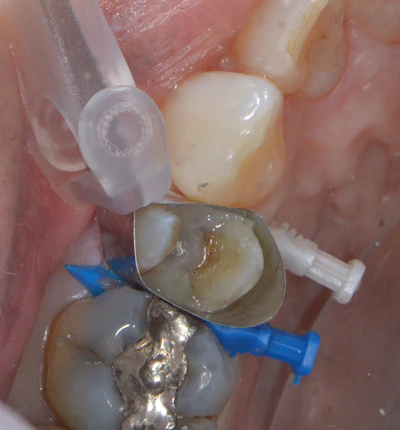

Universal shade or “chameleon” composites aim to simplify this process by providing a streamlined number of shades that blend with a broad range of tooth colors. This is typically achieved through optical properties that allow for color adaptation, allowing the material to blend in with the surrounding tooth structure and translucency that allow for adequate light to pass to the deeper areas for polymerization. That being said, at a depth of 3 mm, Visalys Bulk Flow has a high opaquing capacity, with the ability to mask an underlying amalgam stain and highly chromatic dentin. By effectively masking underlying discoloration while still blending with surrounding tooth structure, the universal shade reduces the need for multiple composite shades or additional, more opaque materials.

Figure 5: Upper premolar with sectional automatrix showing the base layer of Visalys Bulk Flow as an initial increment after 35% phosphoric acid selective etch (Select HV Etch, Bisco) and universal adhesive (All Bond Universal, Bisco). Masking of the underlying dark dentin was achieved with this layer.

In this clinical case, a large failing amalgam was removed from an upper premolar during an emergency visit (Figures 3, 4, 5). The initial pulpal diagnosis was reversible pulpitis. Due to the large crack on the mesial, a composite buildup was placed initially, and the tooth was taken out of occlusion to begin crack stabilization. Endodontics was consulted a few weeks later. For the initial layer of the buildup, Visalys Bulk Flow was placed after a universal adhesive to mask the underlying darkened dentin during this temporary phase of treatment. Figure 3 shows the exceptional opaquing capability of this material.